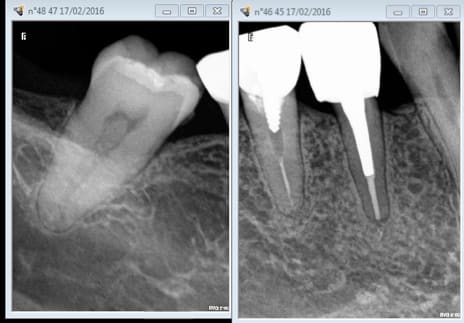

Pour ma part, je ne fais et ne cote de rétro-coronaires que depuis que j'ai viré mon vieux capteur pour un Vistascan. Je n'ai aucun scrupule pour le HBQK443 (4 secteurs, 31.92€).

Et dans ton cas mauvais exemple c'est des rétro alvéolaires qu'il faut faire.

Dans mon cas j'ai une pano de moins de 5 ans donc les BW suffisent en contrôle annuel.

Rétro alvéolaire pour voir l'apex des dents dévitalisées

Même si pano de - de 5 ans

Tu peux faire de mémoire 1 rétro alvéolaire par an puisque adulte à haut risque carieux avec antécédents de soins intensif